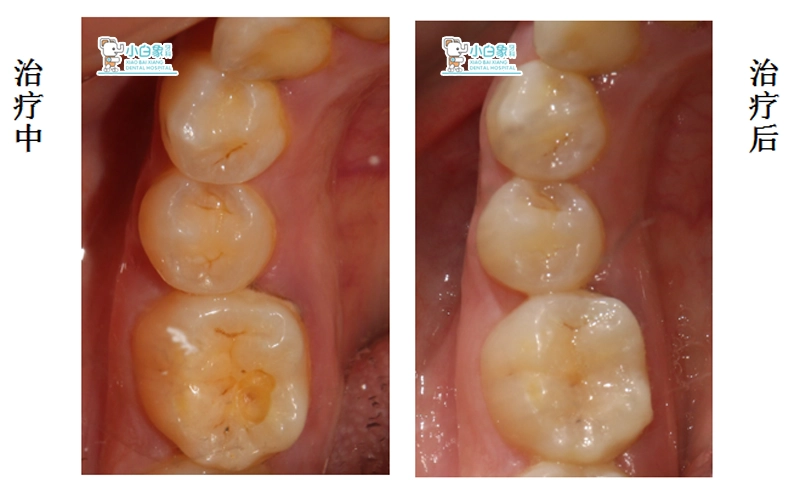

检查:颌面部未见异常,口内查:46合面窝沟龋坏达牙本质浅层,叩(-),探诊无反应,温度测试正常

诊断:46中龋

治疗计划:46充填

治疗过程:46去除腐质,制备洞型,消毒,隔湿干燥,纳米树脂充填,抛光。